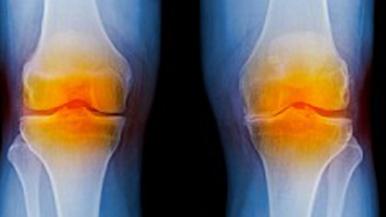

Wear and tear on joints are a natural part of aging — so, too, are the inevitable aches and pains that come with it. Knee pain, in particular, is one of the most common joint problems.

During a total knee replacement, an orthopedic surgeon removes deteriorating joint surfaces and a bit of bone in the knee and replaces them with metal and plastic implants that should last about 20 years.

The most common reason for knee replacement is knee pain from osteoarthritis, rather than a specific trauma to the knee.